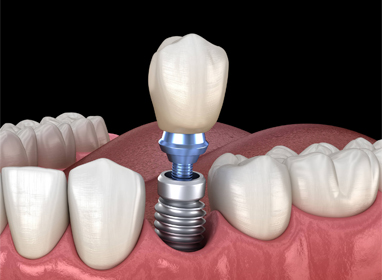

Single Dental Implant

Dental implants start with a small titanium post that is carefully placed in your jawbone—this acts like a brand-new tooth root, providing strength and stability that other tooth replacement options simply can’t match. Over time, the implant fuses naturally with your bone, creating a rock-solid foundation for your new tooth.

Once your implant is secure, Dr. Blake designs a custom dental crown that blends seamlessly with your surrounding teeth, restoring both the look and function of your smile. And thanks to our same-day crown technology, you can often leave our office with your permanent tooth the very same day—no waiting weeks for a lab to finish your crown.